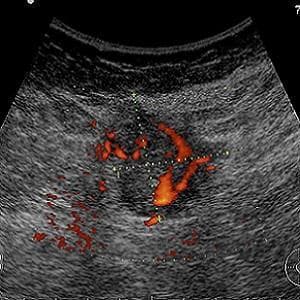

A large study in Japan finds improved rates of detection for breast cancer in women when ultrasound was added to standard mammography tests in breast screening. In addition to accurately detecting more cases of breast cancer, the combo method increased detection rate of early cancers, according to the results published in The Lancet.

Early detection and treatment is critically important for reducing deaths from the disease, and many developed countries have implemented mammography screening programmes for the women who are most at risk. In Asia, breast cancer tends to present at an earlier age than in Europe or the US, and Asian women have denser breast tissue, both of which are known to reduce the accuracy of mammography. As such, detection using standard mammography screening based on European and U.S. practice might miss cases of breast cancer in Asian countries.

Prof. Noriaki Ohuchi, PhD, Tohoku University Graduate School of Medicine (Miyagi, Japan) and colleagues recruited more than 70,000 women in Japan aged between 40 and 49 to participate in the J-START trial. Half were offered the usual mammography screening (control group), and half were offered ultrasound testing in addition to mammography (intervention group), with two screening sessions taking place over two years. The research team reported these key findings:

- Sensitivity, or correct identification of cancer, was significantly higher in the intervention group (91 percent) than in the control group (77 percent);

- More cancers were detected in the intervention group than in the control group (184 vs. 117) and were more frequently stage 0 and 1 (144 vs. 79);

- 18 interval cancers were detected in the intervention group compared with 35 in the control group.

The lower rate of interval cancers — which appear after a negative test result between scheduled rounds of screening — in the intervention group led researchers to conclude that adding ultrasound to mammography screening detected additional cancers, compared to mammography alone.